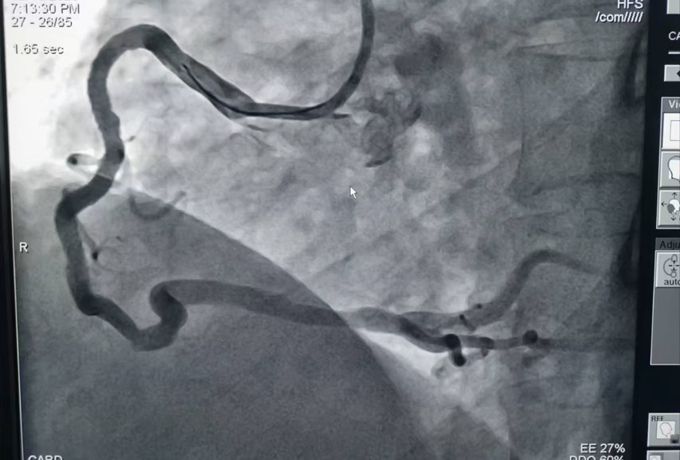

术前造影

为准确判断病情,建议立即行冠脉造影检查。进一步的冠脉造影结果证实了医生的判断,而检查结果也着实让人揪心:患者三支心脏主血管均存在严重弥漫性钙化病变,且严重狭窄,尤其是其中两根较为严重,最重狭窄为次全闭塞。